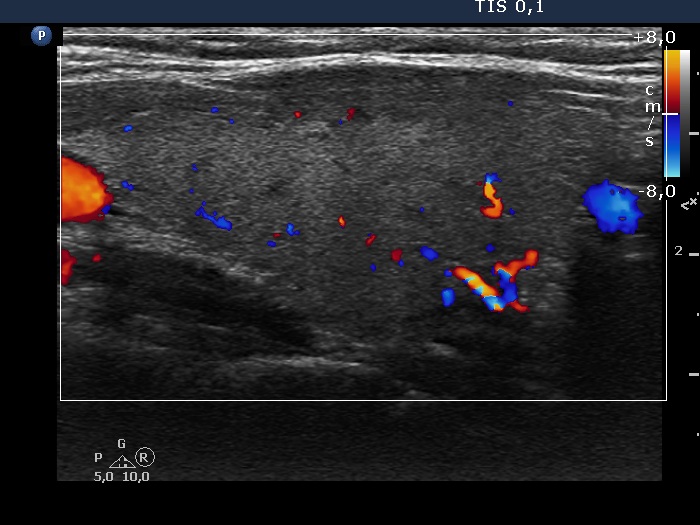

Right lobe, longitudinal scan

Left lobe, lonmgitudinal view, color Doppler mode. There are small vessels within the lobe.